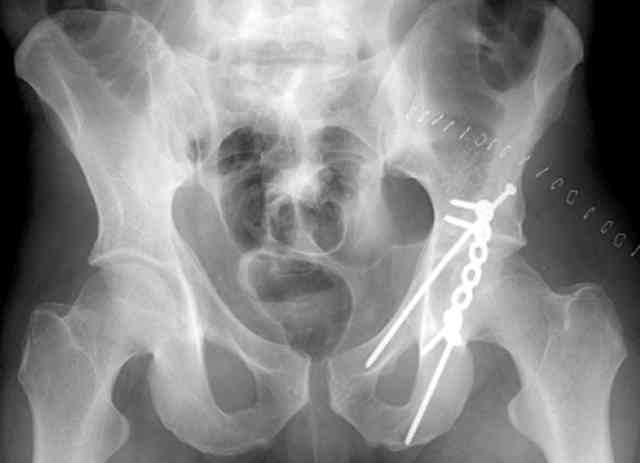

Screw Fixation

-AC Screw

-PC Screw

For Alex... here are some cannulated and 7mm screws for you... notice the fracture malreduction as indicated by the head subluxation on both views...this was a percutaneous technique without open reduction... I don¹t like it but there it is... the fixation technique is not at fault, because there was no open reduction of the fracture... but let¹s not get in to all that.